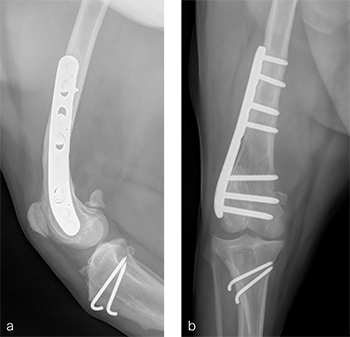

A routine lateral approach to the distal femur and stifle joint was performed. Standard DFO technique was used to create a 10 lateral closing wedge ostectomy. A 7-hole 3.5 LCP DFO plate was placed on the lateral femur and secured with a combination of 3.5 mm cortex and locking screws. The compression function of the plate was used to compress the ends of the two bone segments together. A wedge sulcoplasty was performed to deepen the trochlear groove for improved patella articulation. After routine closure, total surgical time was 1 hour and 30 minutes. Postoperative x-rays demonstrated that plate contour matches the distal femoral procurvatum. The compression applied to the plate results in excellent apposition. The patella is visible within the trochlear groove (Fig 11a). On the craniocadual view, the plate contour matches the anatomical contour of the distal femur. The anatomical Lateral Distal Femoral Angle has been reduced to 94 (Fig 11b). In the 1-year follow up, clinical signs have resolved, limb use is normal and range of motion of the knee is also normal. The osteotomy has healed, plate and screw position remain unchanged, the tibial tuberosity transposition is healing, and implants remain unchanged (Fig 12a). Additionally, the patella remains reduced within the trochlear groove. On the craniocaudal view, the osteotomy has healed and is no longer visible, implants are stable and the patella is tracking normally (Fig 12b).a